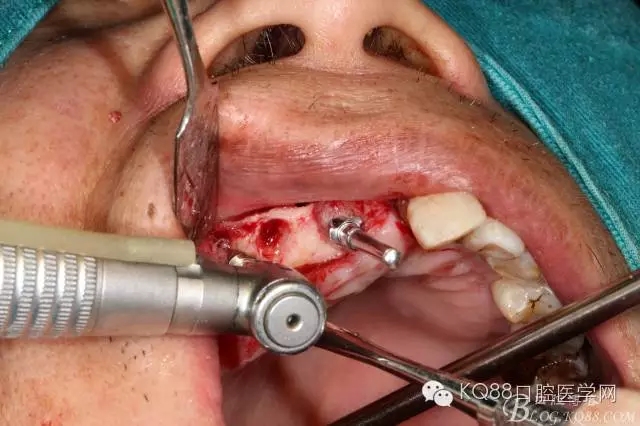

設(shè)計(jì)斜橫切口,從牙槽嵴側(cè)翻開全厚瓣,搔刮牙槽窩內(nèi)肉芽組織,修整牙槽嵴頂。

小球鉆磨除埋伏牙頰側(cè)骨壁,牙挺挺出埋伏牙,清理拔牙窩

金剛砂球鉆制備橢圓形骨窗,遠(yuǎn)中邊緣延伸到上頜結(jié)節(jié),取下骨島,骨角和尖銳的邊緣打磨圓鈍,暴露上頜竇黏膜,分離提升上頜竇黏膜。

定位桿定位,擴(kuò)孔,備洞,bio-oss骨粉和CGF混合后充填竇腔

植入植體,骨島覆蓋上頜骨側(cè)壁骨窗